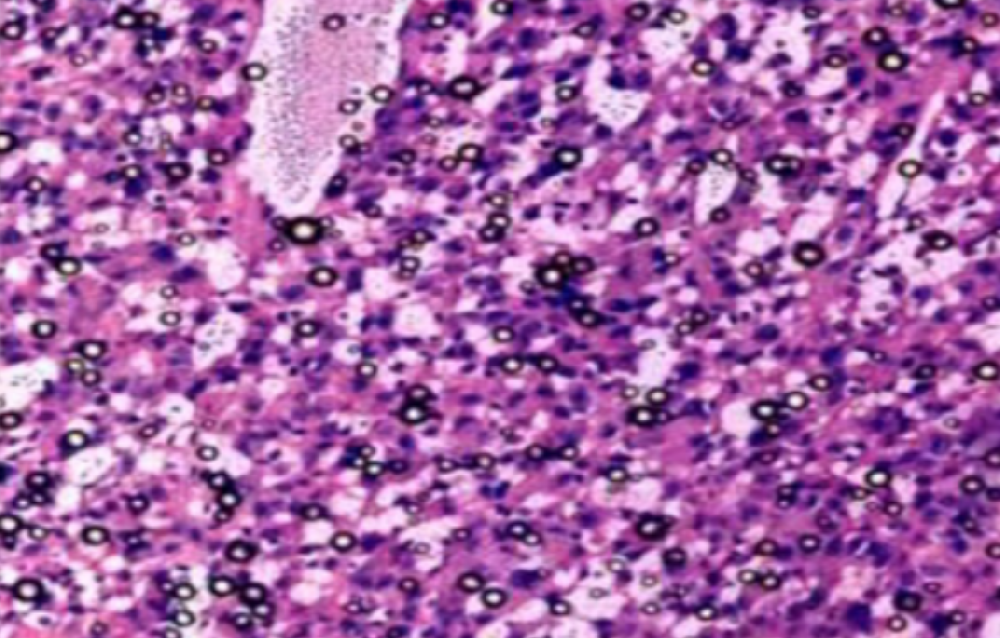

蛋白酶体可通过切割宿主蛋白生成AMPs直接对抗细菌感染

研究背景蛋白酶体是细胞内负责降解泛素化蛋白质的关键复合体,传统认知集中于其维持蛋白质稳态的功能。然而,Goldberg等人的研究揭示了蛋白酶体在抗细菌天然免疫中的全新角···